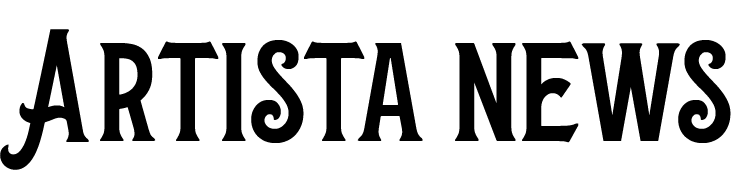

“Il glaucoma – spiega Stefano Miglior, direttore della clinica oculistica Policlinico di Monza, Università Milano Bicocca, nonché Presidente dell’Associazione italiana Studio Glaucoma, è una patologia degenerativa e se non viene monitorata e controllata con la terapia farmacologica o chirurgica porta alla cecità irreversibile. Coinvolge in genere, entrambi gli occhi determinando danni permanenti al nervo ottico. (oggi è la seconda causa di cecità nei Paesi industrializzati).Il fattore di rischio più importante è la pressione oculare elevata, ma in un terzo dei casi viene osservato in pazienti con pressione oculare normale. Il soggetto può andare incontro a una progressiva riduzione del campo visivo fino alla visione cosiddetta “tubulare” che dà l’impressione di guardare attraverso un cono, perché si riesce a vedere solo una piccola parte di ciò che si ha davanti. Non esiste una cura definitiva, ma la patologia può solo essere rallentata. E’ stato osservato che in alcuni pazienti glaucomatosi si assisterebbe anche a una progressiva compromissione strutturale e funzionale di zone cerebrali non propriamente deputate alla visione. Non è raro che le persone non si accorgano, anche per lungo tempo, di esserne affette e arrivino dall’oculista quando la situazione è ormai già compromessa. I controlli oculistici periodici sono fondamentali.”